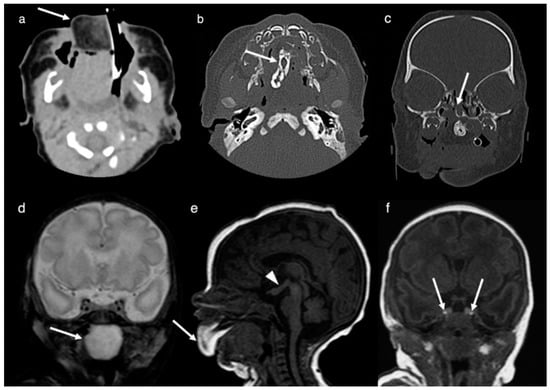

2. Case Report